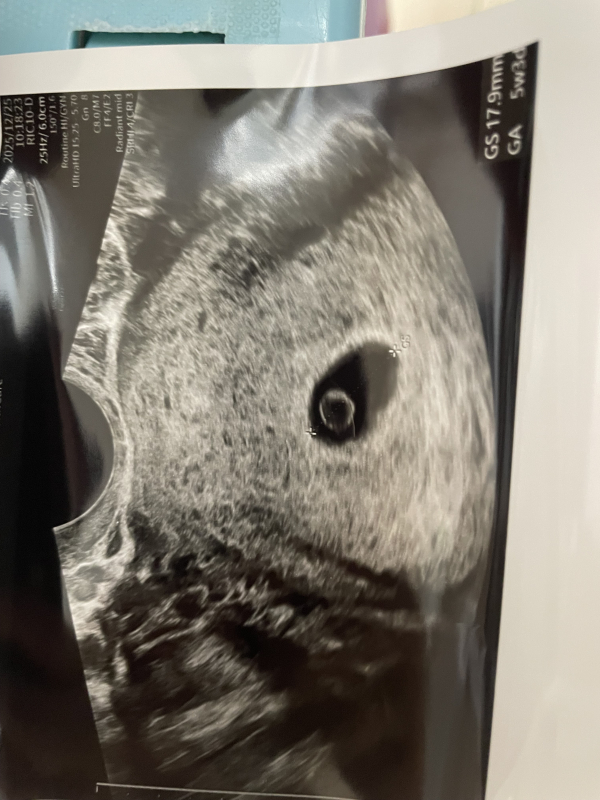

胎嚢と卵黄嚢は5w5dの時に見えました。

今までの流産と違い、胎嚢は9.3㍉あり、初めて先生に小さいね。と言われませんでした。

しかし、12/25の7w3dの妊婦健診の際に、何とか心拍を確認することは出来ましたが、胎芽が小さい。とのこと。

ピクピク心臓が動いているのは分かりましたが、胎芽は2ミリ程でした。